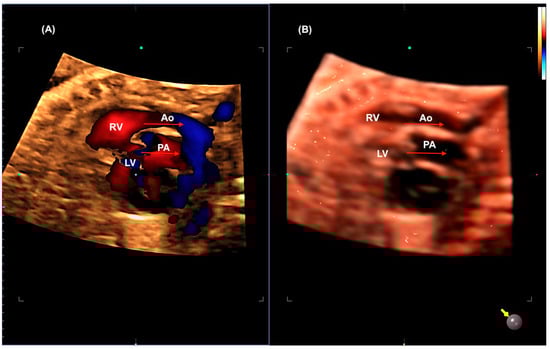

2.2. Transposition of the Great Arteries (TGA)

- Rizzo, G.; Capponi, A.; Cavicchioni, O.; Vendola, M.; Pietrolucci, M.E.; Arduini, D. Application of automated sonography on 4-dimensional volumes of fetuses with transposition of the great arteries. J. Ultrasound Med. 2008, 27, 771–776. [Google Scholar] [CrossRef]

- Shih, J.C.; Shyu, M.K.; Su, Y.N.; Chiang, Y.C.; Lin, C.H.; Lee, C.N. ‘Big-eyed frog’ sign on spatiotemporal image correlation (STIC) in the antenatal diagnosis of transposition of the great arteries. Ultrasound Obstet. Gynecol. 2008, 32, 762–768. [Google Scholar] [CrossRef]